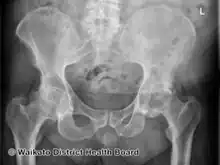

AP Pelvis -